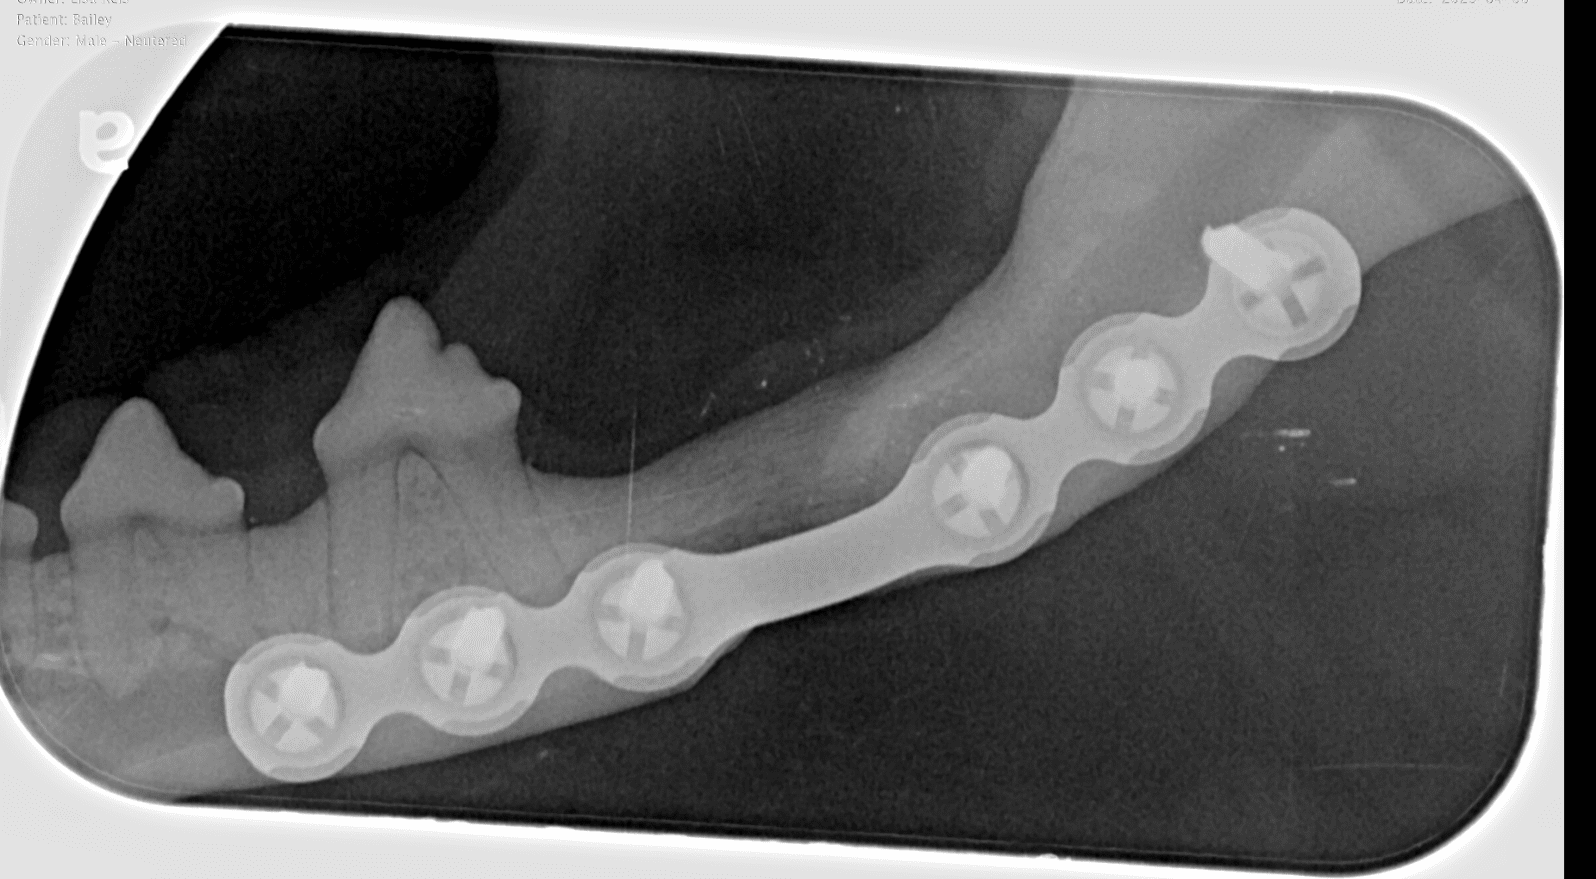

Advanced Oral Surgery

Major and advanced oral surgery such as cleft palate surgery, jaw fracture repair and oral tumor removal.